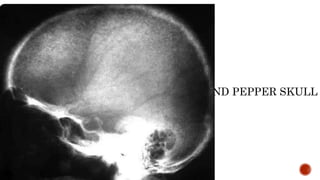

 AP and lateral radiographs of the skull show multiple tiny lucent areas with areas of

sclerosis in between, giving rise to salt and pepper skull appearance.

HYPERPARATHYROIDISM

FINDINGS

 Osteopenia

 Subperiosteal resorption: classically along radial aspects of phalanges

 Floating tooth

 Subchondral resorption (lateral end of clavicles, pubic symphysis, sacroiliac joints)

 Subligamentous resorption(ischial tuberosity, trochanters)

 Brown tumors(more common in primary)

 Salt and pepper skull

 Rugger jersey spine

SALT AND PEPPER SKULL